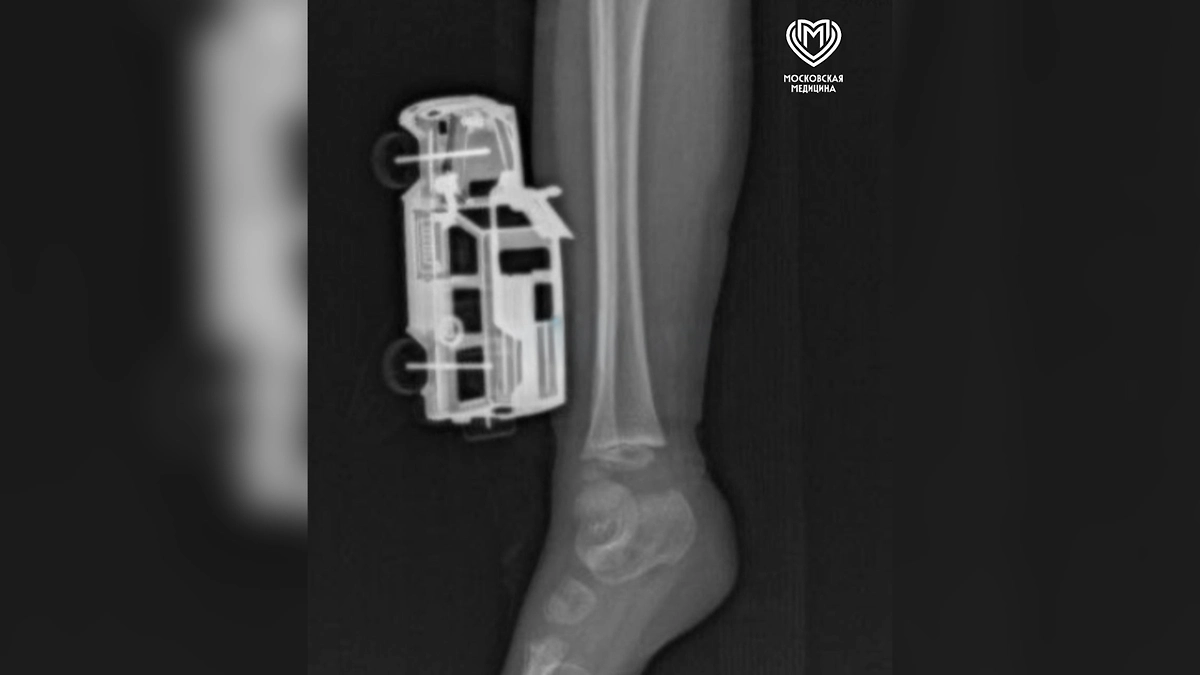

По словам родителей, ребёнок неудачно приземлился после прыжка с кровати прямо на игрушку. Машинка повредила мягкие ткани правой голени, а некоторые части вошли достаточно глубоко в ногу — до подкожножировой клетчатки. Для оценки глубины повреждения и исключения переломов пациенту провели рентгенографическое исследование.

«Маленькому пациенту сделали рентгенографию, чтобы исключить повреждения костей голени и понять глубину повреждения. Затем удалили игрушку и выполнили хирургическую обработку серьёзной раны. Через сутки энергичного детсадовца выписали домой под амбулаторное наблюдение», — рассказал травматолог-ортопед отделения экстренной хирургической помощи Магомед Шихахмедов.